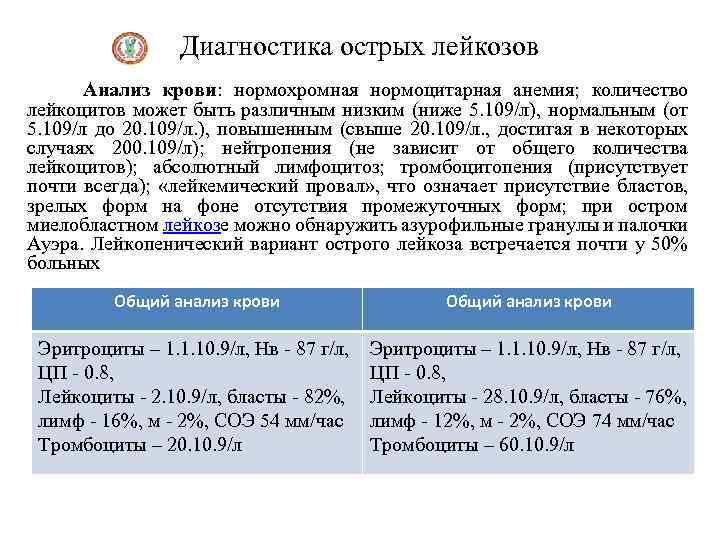

Диагностика острых лейкозов Анализ крови: нормохромная нормоцитарная анемия; количество лейкоцитов может быть различным низким (ниже 5. 109/л), нормальным (от 5. 109/л до 20. 109/л. ), повышенным (свыше 20. 109/л. , достигая в некоторых случаях 200. 109/л); нейтропения (не зависит от общего количества лейкоцитов); абсолютный лимфоцитоз; тромбоцитопения (присутствует почти всегда); «лейкемический провал» , что означает присутствие бластов, зрелых форм на фоне отсутствия промежуточных форм; при остром миелобластном лейкозе можно обнаружить азурофильные гранулы и палочки Ауэра. Лейкопенический вариант острого лейкоза встречается почти у 50% больных Общий анализ крови Эритроциты – 1. 1. 10. 9/л, Нв - 87 г/л, ЦП - 0. 8, Лейкоциты - 2. 10. 9/л, бласты - 82%, лимф - 16%, м - 2%, СОЭ 54 мм/час Тромбоциты – 20. 10. 9/л Эритроциты – 1. 1. 10. 9/л, Нв - 87 г/л, ЦП - 0. 8, Лейкоциты - 28. 10. 9/л, бласты - 76%, лимф - 12%, м - 2%, СОЭ 74 мм/час Тромбоциты – 60. 10. 9/л